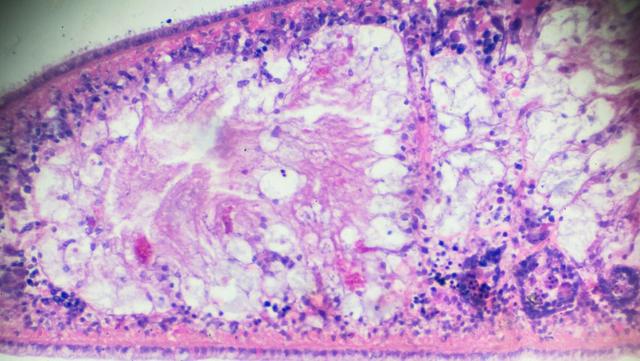

有些人不痒也不痛,但内裤上总是出现一团团像豆腐渣一样的分泌物,别以为是排卵期正常现象,这其实是豆腐渣样白带的典型信号,说明阴道内环境已经被霉菌“霸占”。

除了分泌物异常,有人发现小便时会有灼热感,甚至像针扎一样刺痛,尤其在清洗或性生活后更明显,这说明外阴和阴道黏膜已经被霉菌刺激得不堪重负。